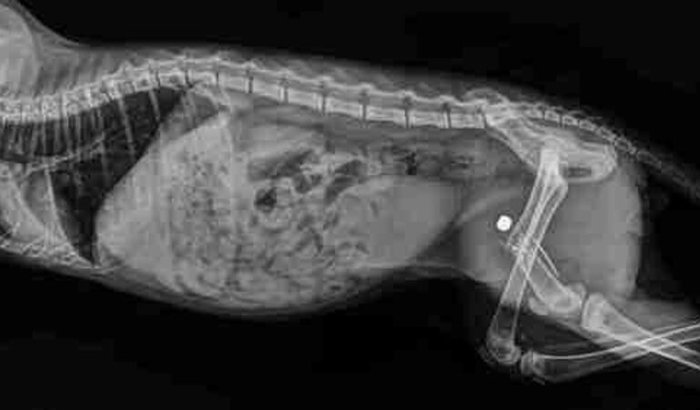

Preciso de ajuda urgente! Esse é meu filho pet (PRETINHO) ontem algum desalmado atirou nele com arma de chumbinho, a bala atravessou sua patinha e quebrou o fêmur, ele é um gatinho muito esperto e brincalhão, e não está conseguindo andar ver tudo

Preciso de ajuda urgente! Esse é meu filho pet (PRETINHO) ontem algum desalmado atirou nele com arma de chumbinho, a bala atravessou sua patinha e quebrou o fêmur, ele é um gatinho muito esperto e brincalhão, e não está conseguindo andar, precisa urgente fazer uma cirurgia para retirar o projétil de sua patinha e reconstruir o ossinho. Peço a ajuda de vocês, eu preciso arrecadar 1600,00. Nas fotos tem o orçamento, RX e exames. Quem puder me ajudar com qualquer quantia, ficarei imensamente grata. chave Pix ffabicf@gmail.com